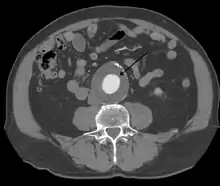

The diagnosis of an abdominal aortic aneurysm can be confirmed by the use of ultrasound. Rupture may be indicated by the presence of free fluid in the abdomen. A contrast-enhanced abdominal CT scan is the best test to diagnose an AAA and guide treatment options.[10]

A large, rapidly expanding, or symptomatic aneurysm should be repaired, as it has a greater chance of rupture. Slowly expanding aortic aneurysms may be followed by routine diagnostic testing (i.e.: CT scan or ultrasound imaging).